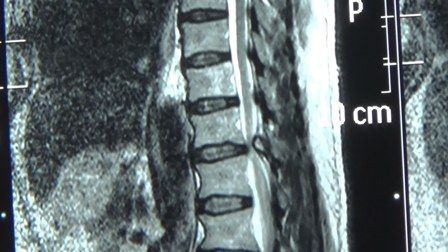

核心提示:骨血管瘤是一种呈瘤样增生的血管组织,掺杂于骨小梁之间,不易将其单独分离。从组织学上分为海绵状血管瘤及毛细血管瘤,前者多见于脊柱和颅骨,后者多见于扁骨和长管状骨干骺部。跟着小编去认识一下关于骨血管瘤的相...